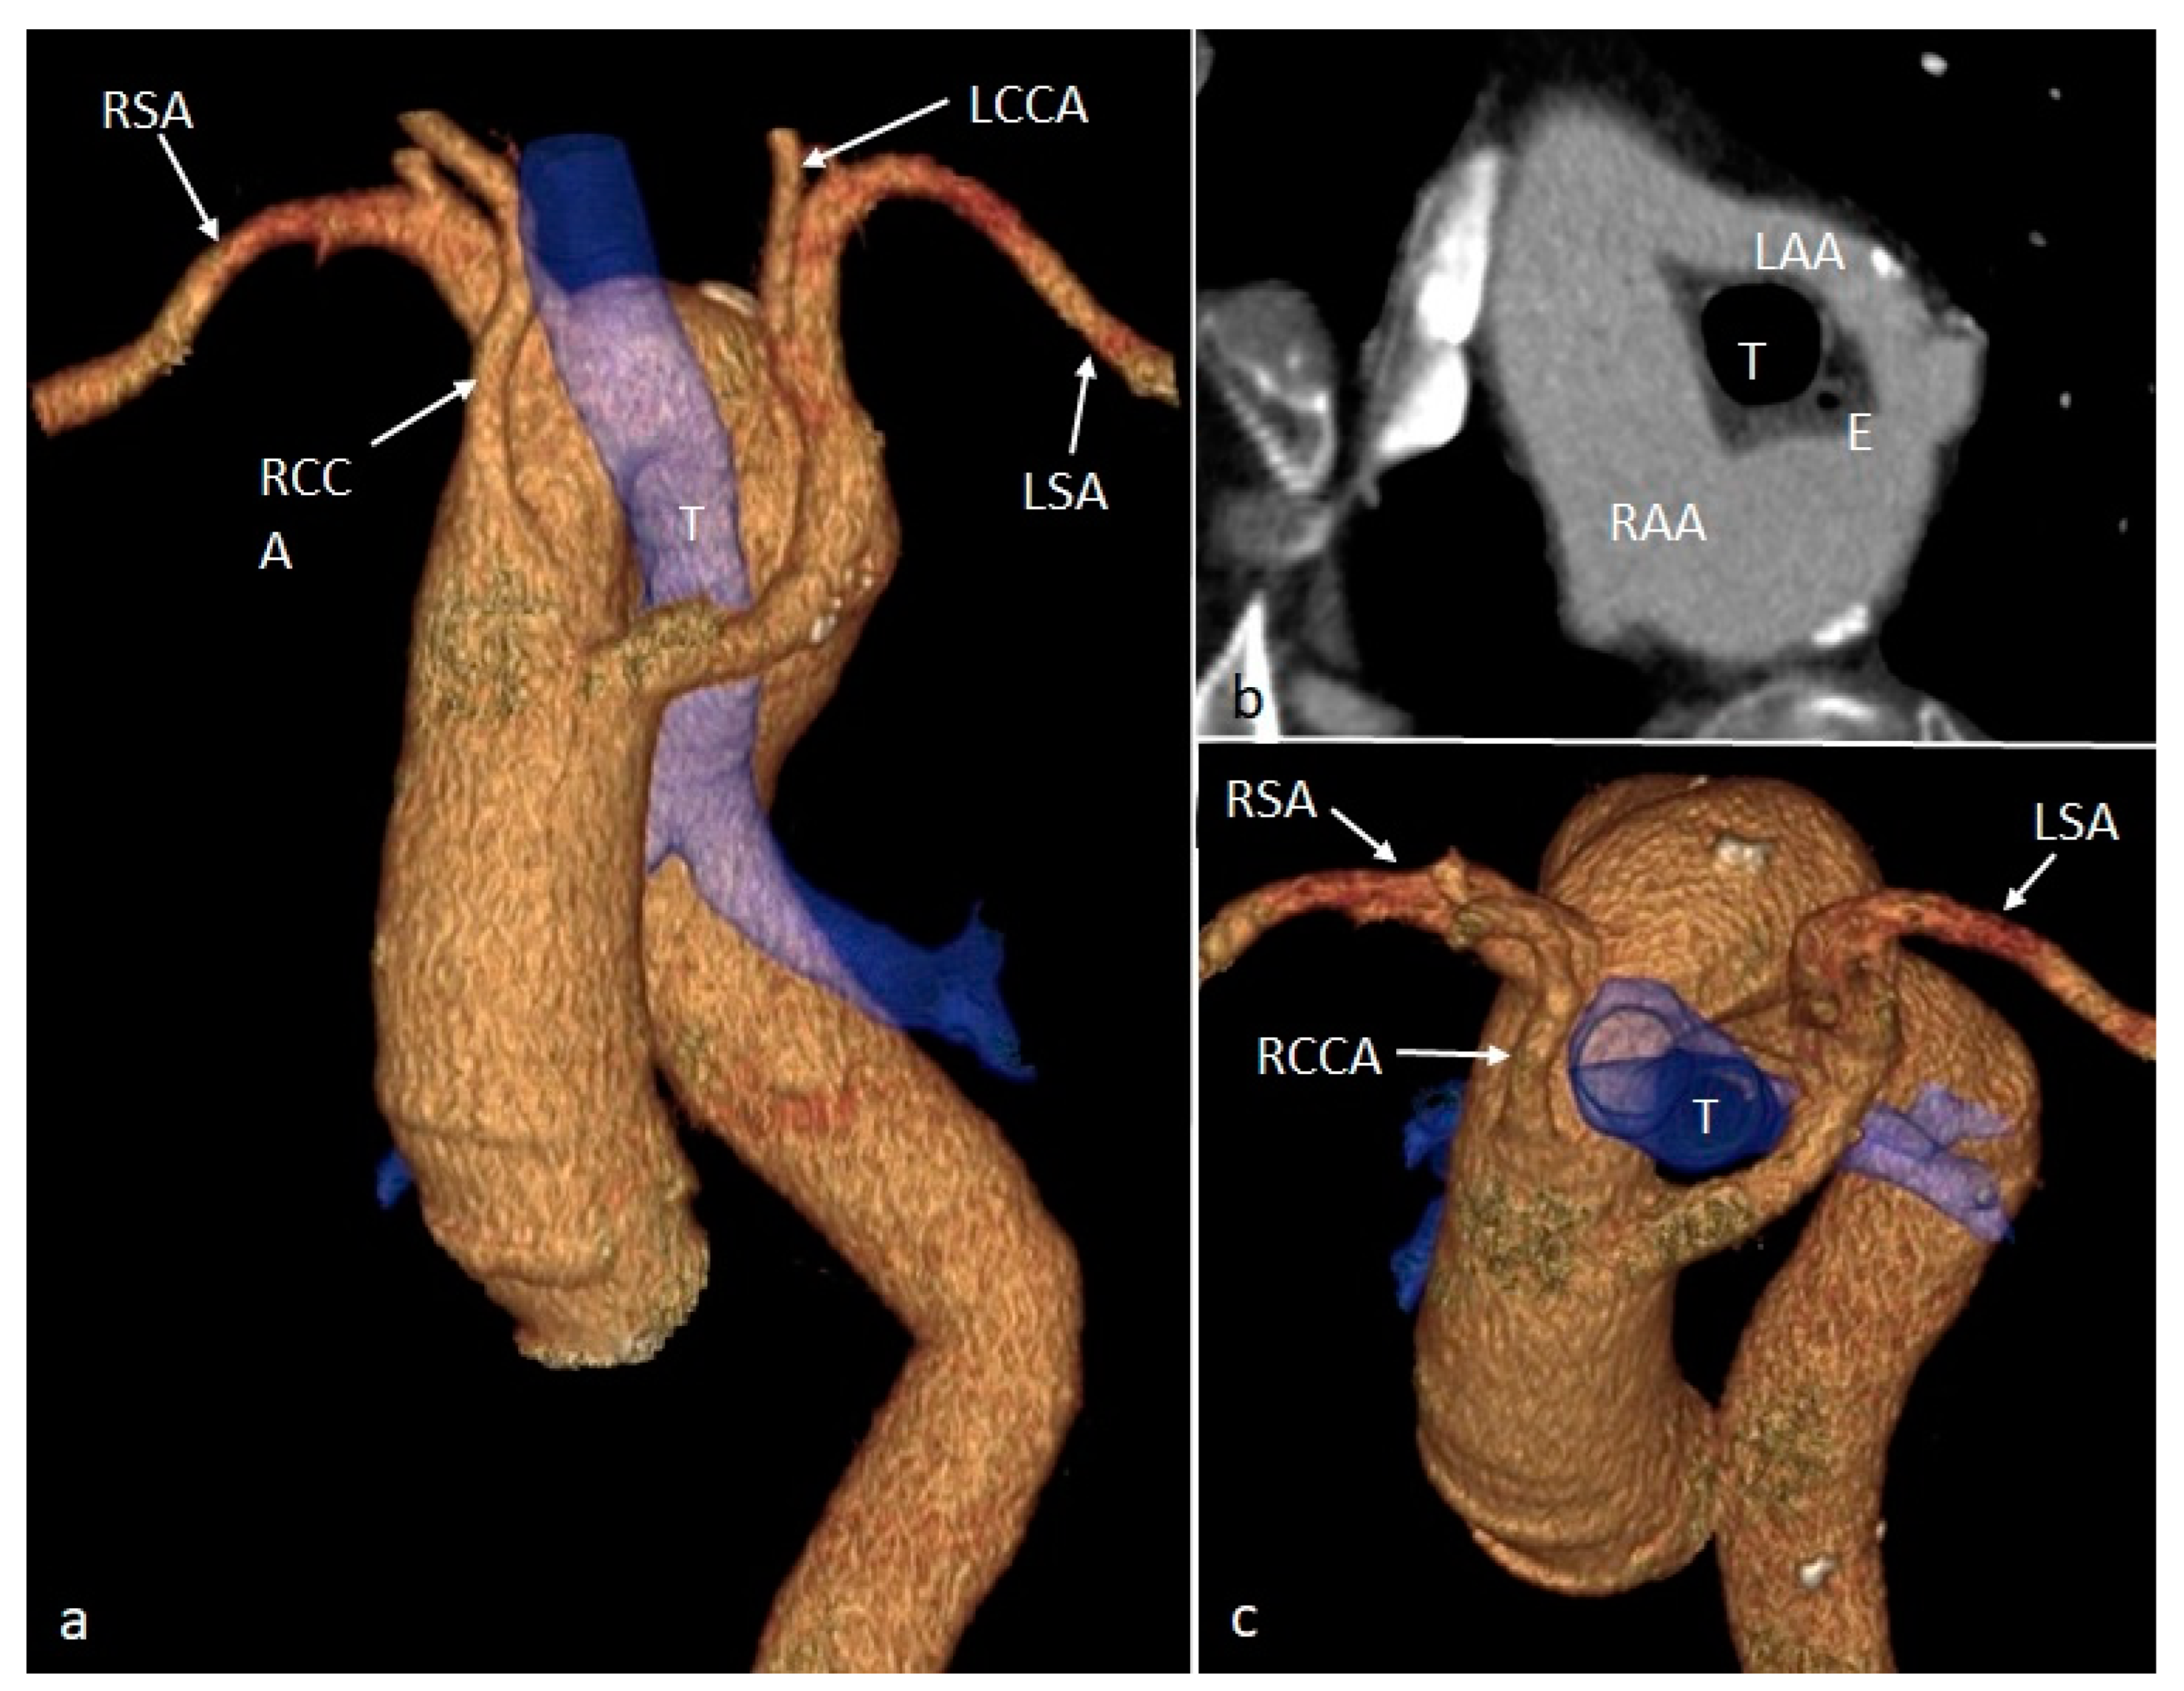

| RAA | Right aortic arch |

| RCCA | Right common carotid artery |

| RSA | Right subclavian artery |

| DA | Descending aorta |

| PA | Pulmonary artery |